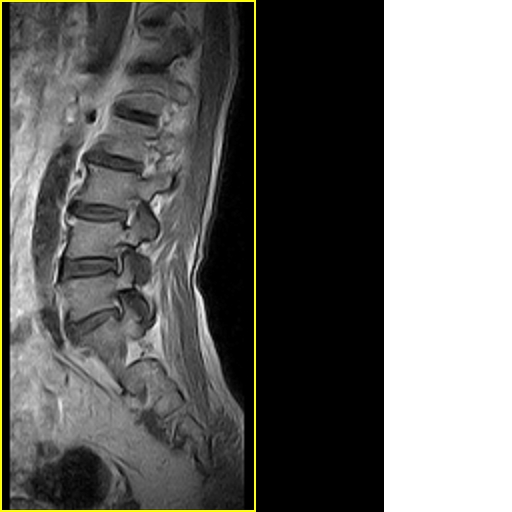

男,78岁,右下肢跛行两月.

退行性骨关节病:增生、椎间盘变性、膨出...

退行性病变:增生、椎间盘变性、膨出[l4-5、l5-s1 椎间盘膨出]

退行性骨关节病:增生、椎间盘变性、膨出..黄韧带肥厚.